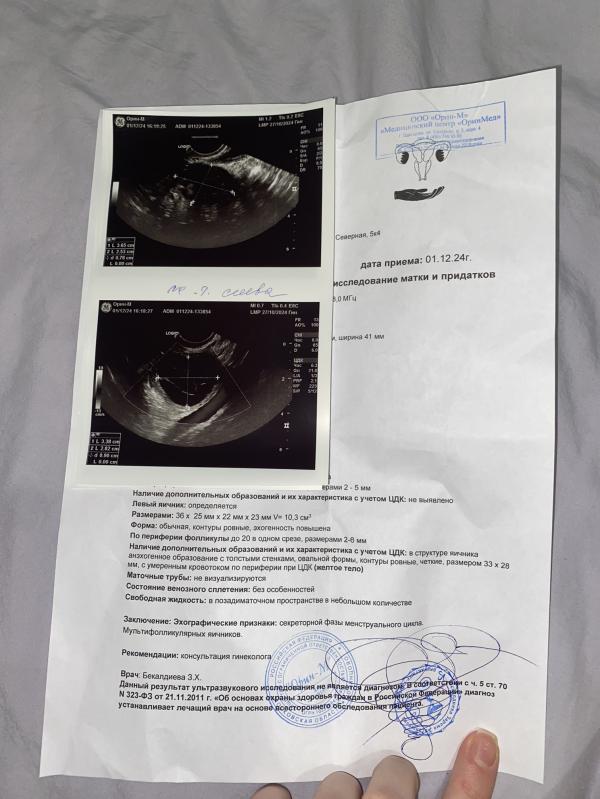

Тут пишет в левом яичнике анэхогенное образования размер 33мм это может быть киста желтого тела и вероятно задержка из за этого

Эндик хороший, желтое тело большое, скорее всего киста. Фолликулов много в срезе, похоже на мфя

@heda.2525, и вроде как овуляция была, так как есть жидкость в позадиматочном пространстве, но образовалась киста